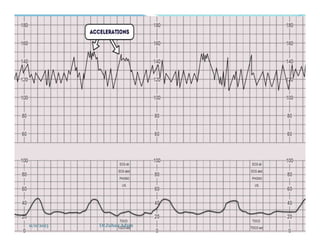

Accelerations

 Define accelerations as transient increases in fetal heart

rate of 15 beats a minute or more, lasting 15 seconds or

more.

 Take the following into account when assessing

accelerations in fetal heart rate:

 • the presence of fetal heart rate accelerations, even with

reduced variability, is generally a sign that the baby is

healthy

 • the absence of accelerations on an otherwise normal CTG

trace does not indicate fetal acidosi